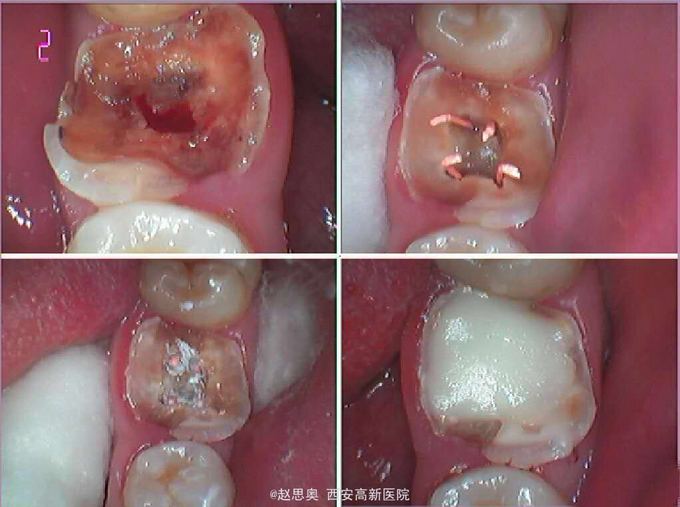

诊断为不可复性牙髓炎,慢性根尖周炎 处理,根管治疗后间接树脂修复

自我评价:感觉窝沟走形不好,窝沟深度不协调,牙尖分布不够好。预后情况和患者交代清楚,告知 术后隐患,定期复诊。 术后思考:意见1、用单反相机拍摄口内同名牙及邻牙照片,堆塑时放大照片用以参考窝沟走形及牙尖斜度 弧度。